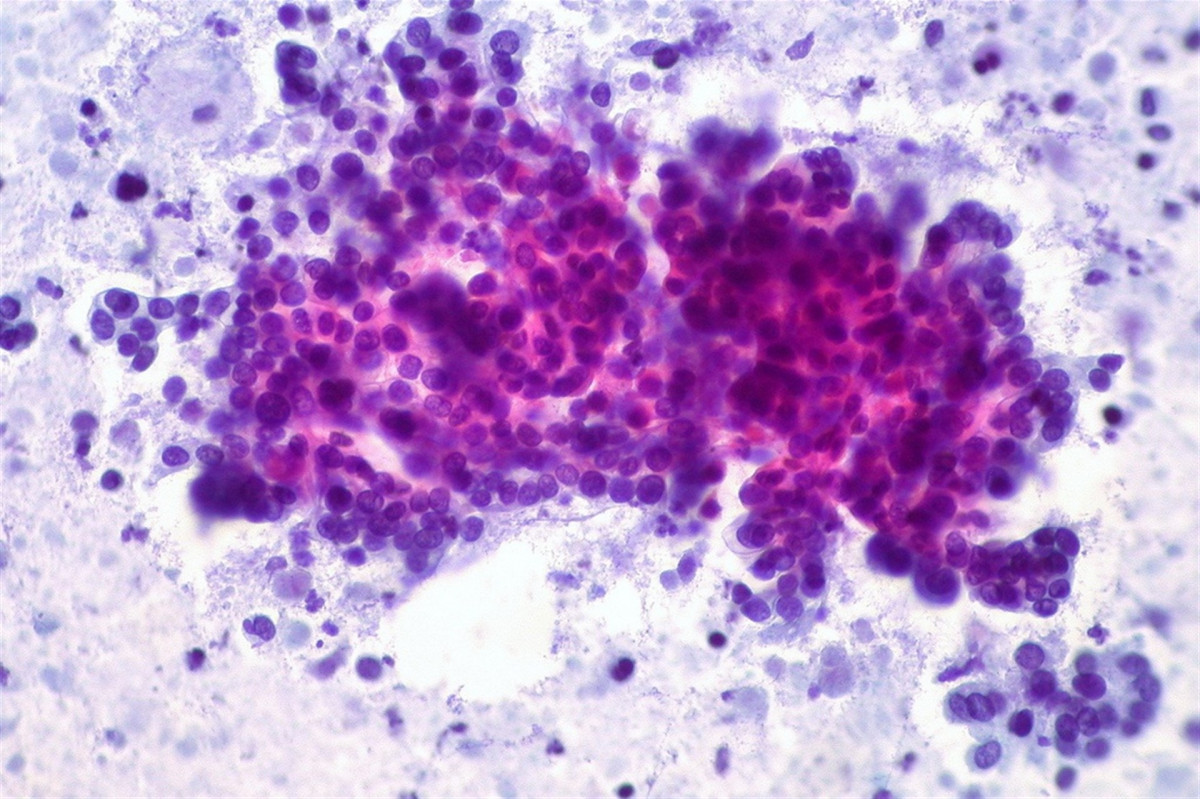

Un equipo liderado por científicos del Instituto de Investigación Van Andel (Estados Unidos) ha desarrollado un nuevo y simple análisis de sangre que, cuando se combina con la prueba ya existente, detecta casi el 70 por ciento de los cánceres de páncreas con una tasa de falsos positivos de menos del 5 por ciento.

Este nuevo enfoque para la detección del cáncer de páncreas, cuyos pormenores han sido detallados en una artículo en la revista 'Clinical Cancer Research', puede ayudar a los médicos a detectar la enfermedad en personas con alto riesgo antes de que alcancen etapas más avanzadas y difíciles de tratar.

El cáncer de páncreas es difícil de diagnosticar porque a menudo no presenta síntomas precoces. En el momento en que se detecta la enfermedad, generalmente está bastante avanzada, lo que complica el tratamiento y conduce a resultados más deficientes. Solo el 8,5 por ciento de las personas con cáncer de páncreas sobreviven más de cinco años, una cifra que ha aumentado ligeramente desde principios de los años 90.

Ambas pruebas detectan y miden los niveles de azúcares producidos por células de cáncer de páncreas que posteriormente se escapan al torrente sanguíneo. El azúcar medido por la nueva prueba, denominada sTRA, es producido por un subconjunto diferente de cánceres pancreáticos que el CA-19-9, el azúcar medido por la prueba ya existente. Cuando se usan juntas, las pruebas proyectan una red más amplia y detectan subtipos de cáncer de páncreas que pueden haberse perdido al usar una de las dos pruebas por sí sola.

CA-19-9 se desarrolló hace casi 40 años y detecta solo alrededor del 40 por ciento de los cánceres de páncreas. Actualmente se usa para confirmar el diagnóstico de cáncer de páncreas o rastrear la progresión de la enfermedad en lugar de detectar la enfermedad. La mejor tasa de detección que ofrece el uso combinado de las pruebas sTRA y CA-19-9 hace que este enfoque sea una opción viable para la detección e intervención temprana, especialmente en personas que tienen un mayor riesgo de desarrollar la enfermedad.